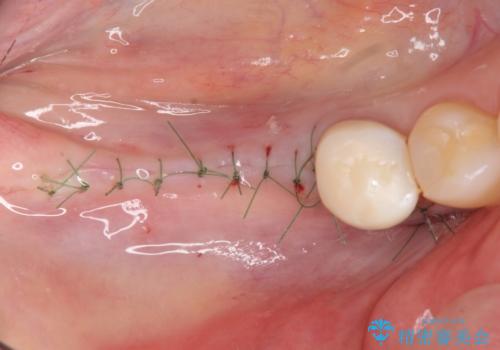

- 失ってしまった奥歯の咬合機能の回復を求めて来院されました。

骨の幅が十分にないのでインプラント治療に伴い、人工骨の造成を同時に計画します。

長年安心してしっかりと噛んでいただけるよう今回は骨を増成する治療計画としました。

- 外科手術のため、術後に痛みや腫れ、違和感を伴います